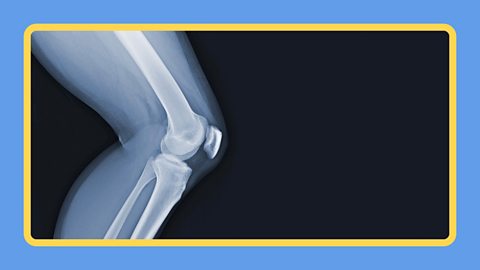

The bones in your skeleton help you stay standing up and let you move around.

You have legs, knees, feet and toes.

Knee – The joint that allows your leg to bend.

Legs – The limbs that support your body and help you to move.